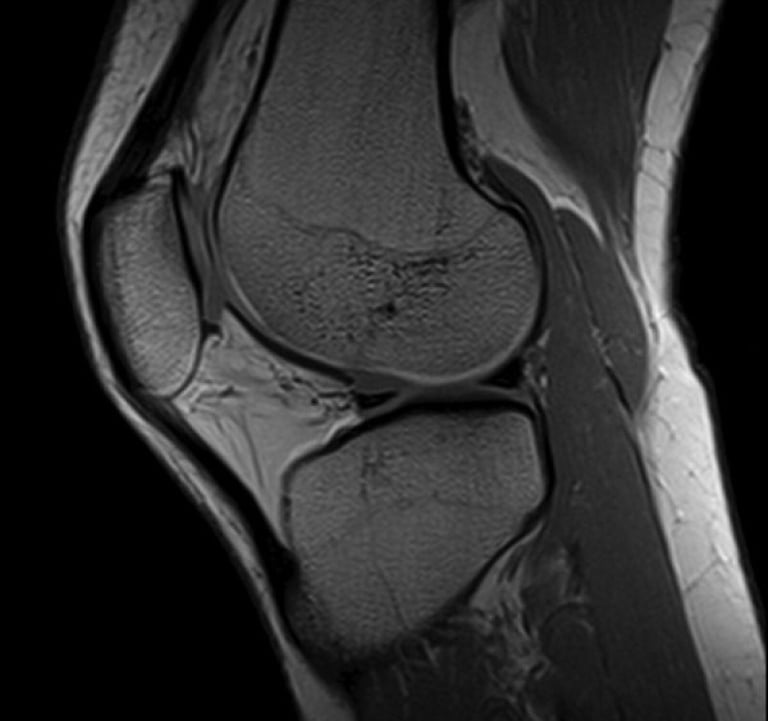

RADIOLOGÍA

El área de radiología, con docentes altamente calificados para brindarte lo mejor en esta nueva era de la inteligencia artificial y cómo cambia todo lo que sabemos del área, además de tener contenido de radiología, también habrá informática. x contenido de radiología para mantenernos actualizados en todo lo relacionado con PACS, HIS, LIS, RIS.